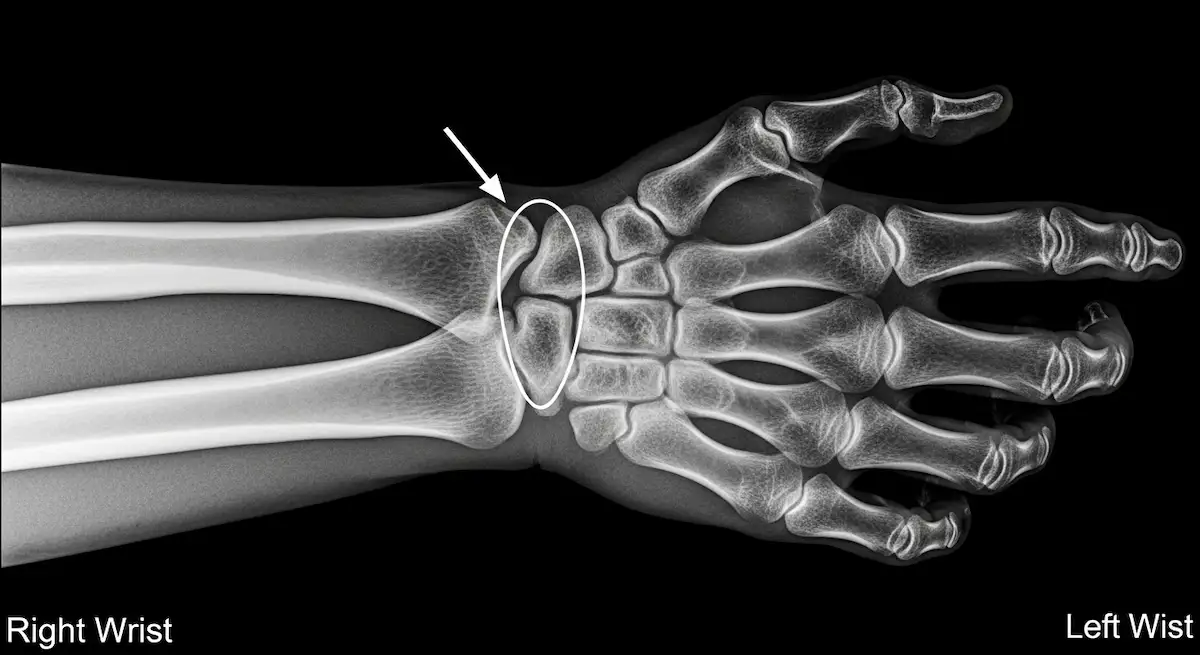

A Síndrome do Canal de Guyon é uma neuropatia compressiva do nervo ulnar no punho. O canal é formado por ossos do carpo e ligamentos, conduzindo o nervo e a artéria ulnar até a mão.

Quando existe estreitamento, cisto, edema ou sobrecarga mecânica, o nervo perde condução, surgindo alteração de sensibilidade e déficit motor dos músculos intrínsecos.

O diagnóstico da Síndrome do Canal de Guyon começa pela história clínica e exame físico com testes de provocação e digitopercussão sobre o canal.

- A ultrassonografia detecta espessamento do nervo e pesquisa cistos.

- Radiografias avaliam fraturas e artrose.